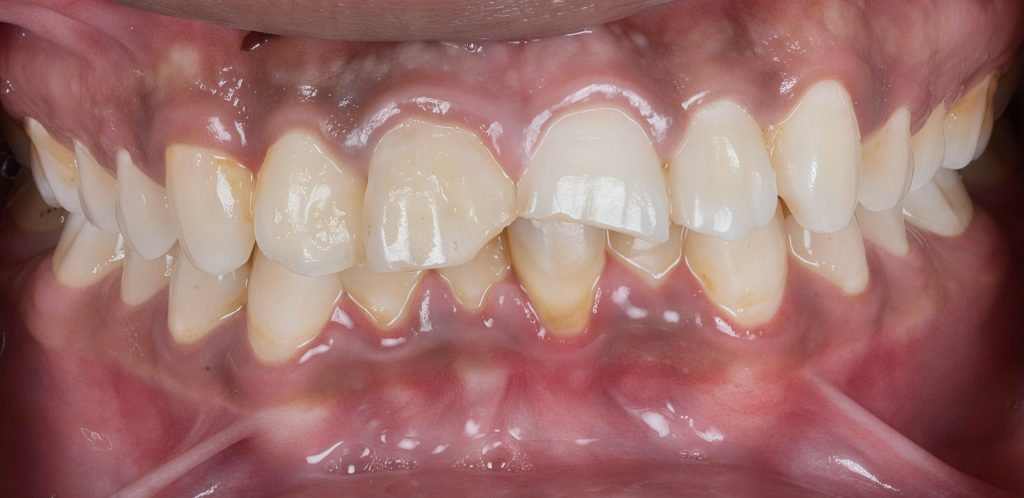

A young adult male presented complaining of aesthetic impairment following previous anterior trauma. His chief concerns included:

- Visible enamel fractures

- Edge chipping and uneven incisal display

- Lack of smile symmetry

- Spaces affecting appearance

Intraoral Findings

- Teeth involved: 11 and 21 (FDI system)

- Trauma history: uncomplicated enamel–dentine fracture

- Pulp vitality: within normal limits

- Periodontal status: healthy

- Occlusion: Class I with stable guidance

- Tooth preparation tolerance: refused ceramic veneers

- Patient request: zero enamel removal

Full arch rubber dam isolation was placed to secure a sterile adhesive environment and retract soft tissue. (Fig.1)